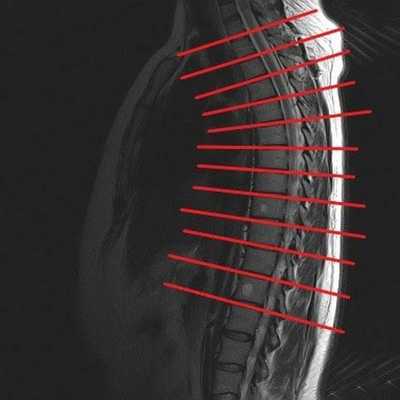

МРТ грудного отдела в сагиттальной проекции, линии разделяют позвонки Th1-12

- размер, конфигурацию, взаимное расположение Th1-Th12 позвонков;

Оценивая состояние грудного отдела, врач указывает локализацию возможных патологических очагов в соответствии с названием расположенного рядом позвонка (Th1-12). Протокол исследования содержит информацию о размерах измененного участка, интенсивности сигнала и природе заболевания.